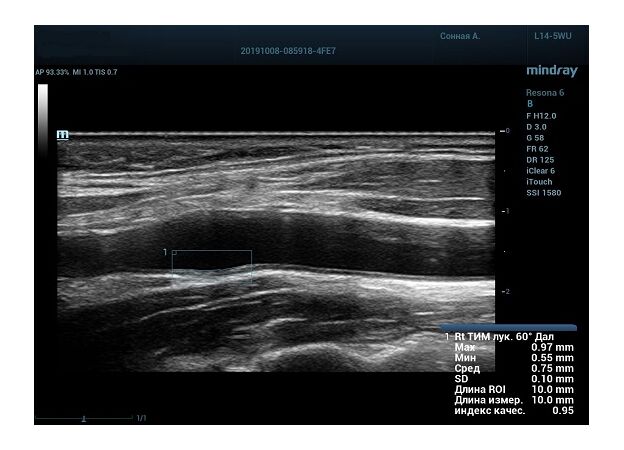

На сегодняшний день измерение IMT происходит автоматическим путем при использовании функции AUTO-IMT. Необходимо указать прибору зону интереса, стандартной длиной (1 см), в которой происходит отслеживание кромок и выдача максимального, среднего и минимального значения. УЗИ аппараты компании Mindray среднего, экспертного и премиального класса снабжены данной функцией и позволяют контролировать не только полученные значения, но и оценить точность измерения кромки в конкретной зоне по индексу качества. Используя индекс качества, легко решить, можно ли использовать полученное значение.